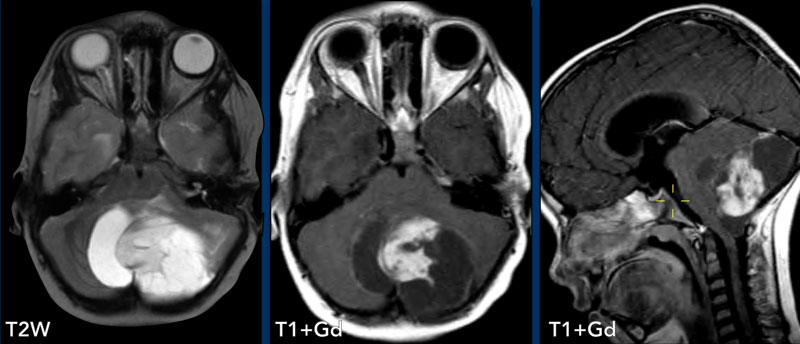

9岁男孩,髓母细胞瘤,软脑膜播散转移,多发线样强化,伴结节状强化。桥脑前缘可见“糖衣”征。